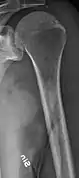

The diagnostic examination of a person with suspected multiple myeloma typically includes a skeletal survey. This is a series of X-rays of the skull, axial skeleton, and proximal long bones. Myeloma activity sometimes appears as "lytic lesions" (with local disappearance of normal bone due to resorption) or as "punched-out lesions" on the skull X-ray ("raindrop skull"). Lesions may also be sclerotic, which is seen as radiodense.[70] Overall, the radiodensity of myeloma is between −30 and 120 Hounsfield units (HU).[71] Magnetic resonance imaging is more sensitive than simple X-rays in the detection of lytic lesions, and may supersede a skeletal survey, especially when vertebral disease is suspected. Occasionally, a CT scan is performed to measure the size of soft-tissue plasmacytomas. Nuclear Medicine Bone scans are typically not of any additional value in the workup of people with myeloma (no new bone formation; lytic lesions not well visualized on nuclear bone scan).

- Humerus with multiple myeloma lesions

- Same humerus before, with just subtle lesions